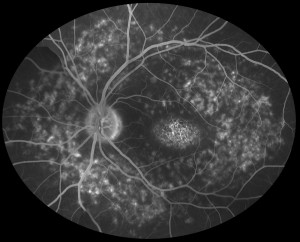

El propósito de este trabajo fue estudiar el rendimiento de lectura de los pacientes con enfermedad de Stargardt, y la relación entre las mediciones clínicas de la visión y la calidad de vida relacionada con la visión.

Se estudiaron ambos ojos de 16 pacientes con enfermedad de Stargardt. A cada paciente se le examinó la agudeza visual corregida (ETDRS), la capacidad de lectura (tablas MNREAD y REX),la sensibilidad al contraste (test Pelli-Robson), el estudio de fijación (microperímetro MP1), y la relación visión-calidad de vida ( test NEI VFQ-25). El patrón de correlación entre estas variables se examinó y se utilizó un análisis factorial exploratorio para investigar dimensionalidad tanto de la función visual y la calidad de vida relacionada con la visión.

La media de agudeza visual (ETDRS) fue de aproximadamente 20/160 (0,9 logMAR). Todas las medidas psicofísicas estudiadas fueron altamente o moderadamente correlacionadas con la velocidad de lectura MNREAD (p <0,05). Se encontró una correlación similar entre las medidas psicofísicas y las de calidad de vida, que fue superior para las medidas de agudeza (r = -0,75) y velocidad (r = 0,74) en la lectura. En consecuencia, el análisis factorial exploratorio sugiere que una sola dimensión latente explica la mayor parte de la varianza de medidas psicofísicas de visión, así como de la calidad de vida relacionada con la visión.

En conclusión, la capacidad de lectura debe ser evaluada en pacientes con enfermedad de Stargardt, ya que encontramos que tanto la velocidad de lectura y la agudeza visual son fuertes determinantes de la calidad de vida.

La relación observada entre la capacidad de lectura y la calidad de vida en pacientes con Stargardt sugiere que en estos pacientes la Rehabilitación de Baja Visión apropiada e individualizada para cada caso puede mejorar el rendimiento de lectura y, en consecuencia la calidad de sus vidas.

Por último, estos datos apoyan el uso de la velocidad de lectura y la agudeza visual como medidas de resultado importantes para la progresión y vigilancia de la enfermedad de Stargardt.